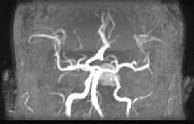

问题 男性,55岁,头痛一年余,两个小时前突然出现剧烈头痛,MRI检查如图所示,最可能的诊断为()

选项 A.垂体瘤 B.脑膜瘤 C.颅咽管瘤 D.垂体瘤并卒中 E.动脉瘤

答案 D